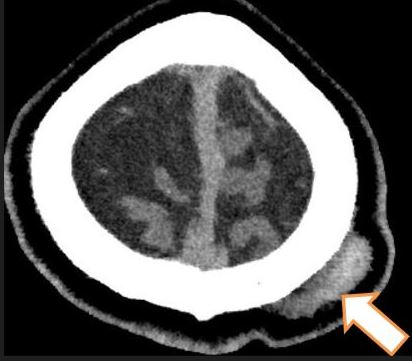

- CT brain – 11 June. Day 2 post mild head injury (after second fall).

Bilateral fronto- parietal hypodense subdural hemorrhage / effusion widest at frontal region, right measures 10 mm keft measures 13 mm in thickness.

There is hyperdense component seen at right parietal region (9 mm in thickness). Mild enhancement of the sulci bilaterally.

Left parietal scalp swelling.

Impression: Bilateral fronto-parietal subdural hemorrhage as described.

- CT brain. Comparison made with CT brain yesterday – 12 June 2024.

Impression: Right parietal extra-axil haemorrhage, stable in size compared to previous.

Bilateral fronto-temporo-parietal subdural hygroma.